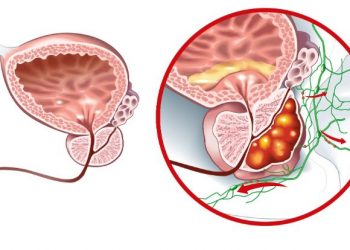

סרטן הערמונית سرطان البروستاتا ، ويسمى أيضًا سرطان البروستاتا ، هو اضطراب في البروستاتا يحدث في غدة البروستاتا. تعد سرطانات...